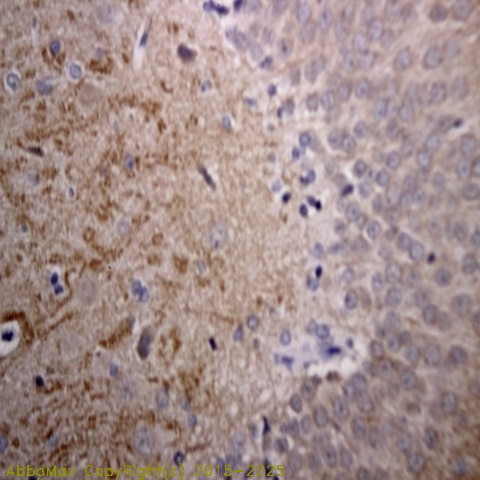

Synuclein Alpha (pS129)

IHC

2-10 µg/ml

Applications: IHC(P), WB